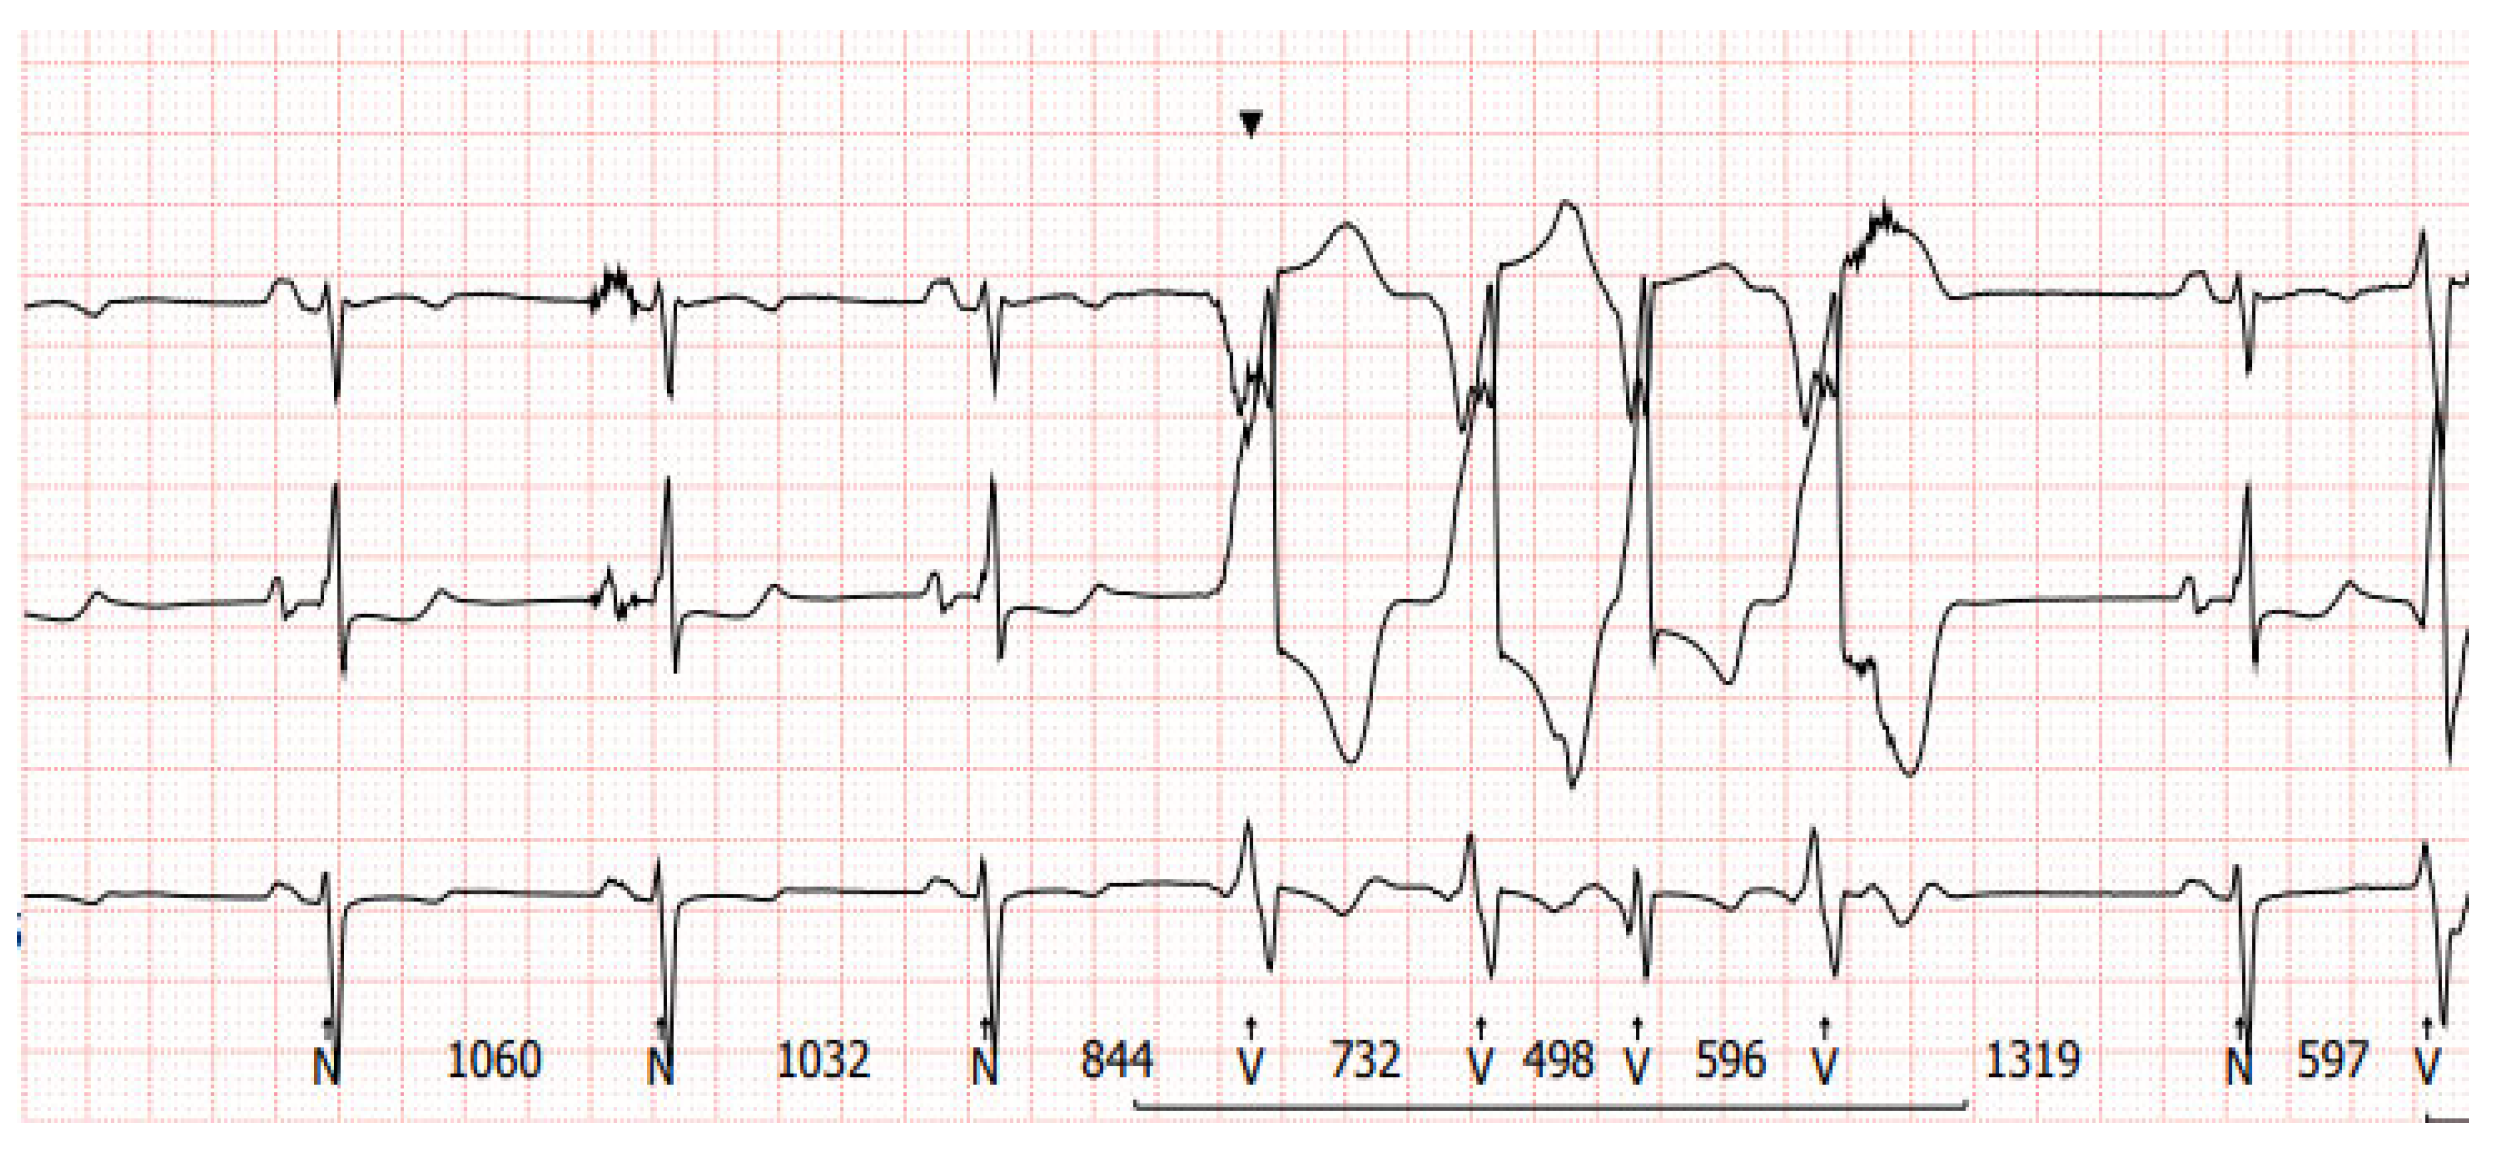

2. Diagnostic Difficulties of Ventricular Arrhythmias in Patients with Left Ventricular Assist Device

3. Electrocardiography in Patients with Implanted LVADs

3.1. Twelve-Lead ECG Findings in Patients with LVADs

3.2. Alternative Diagnostic Methods of Noninvasive Electrocardiography in Patients with Implanted LVADs